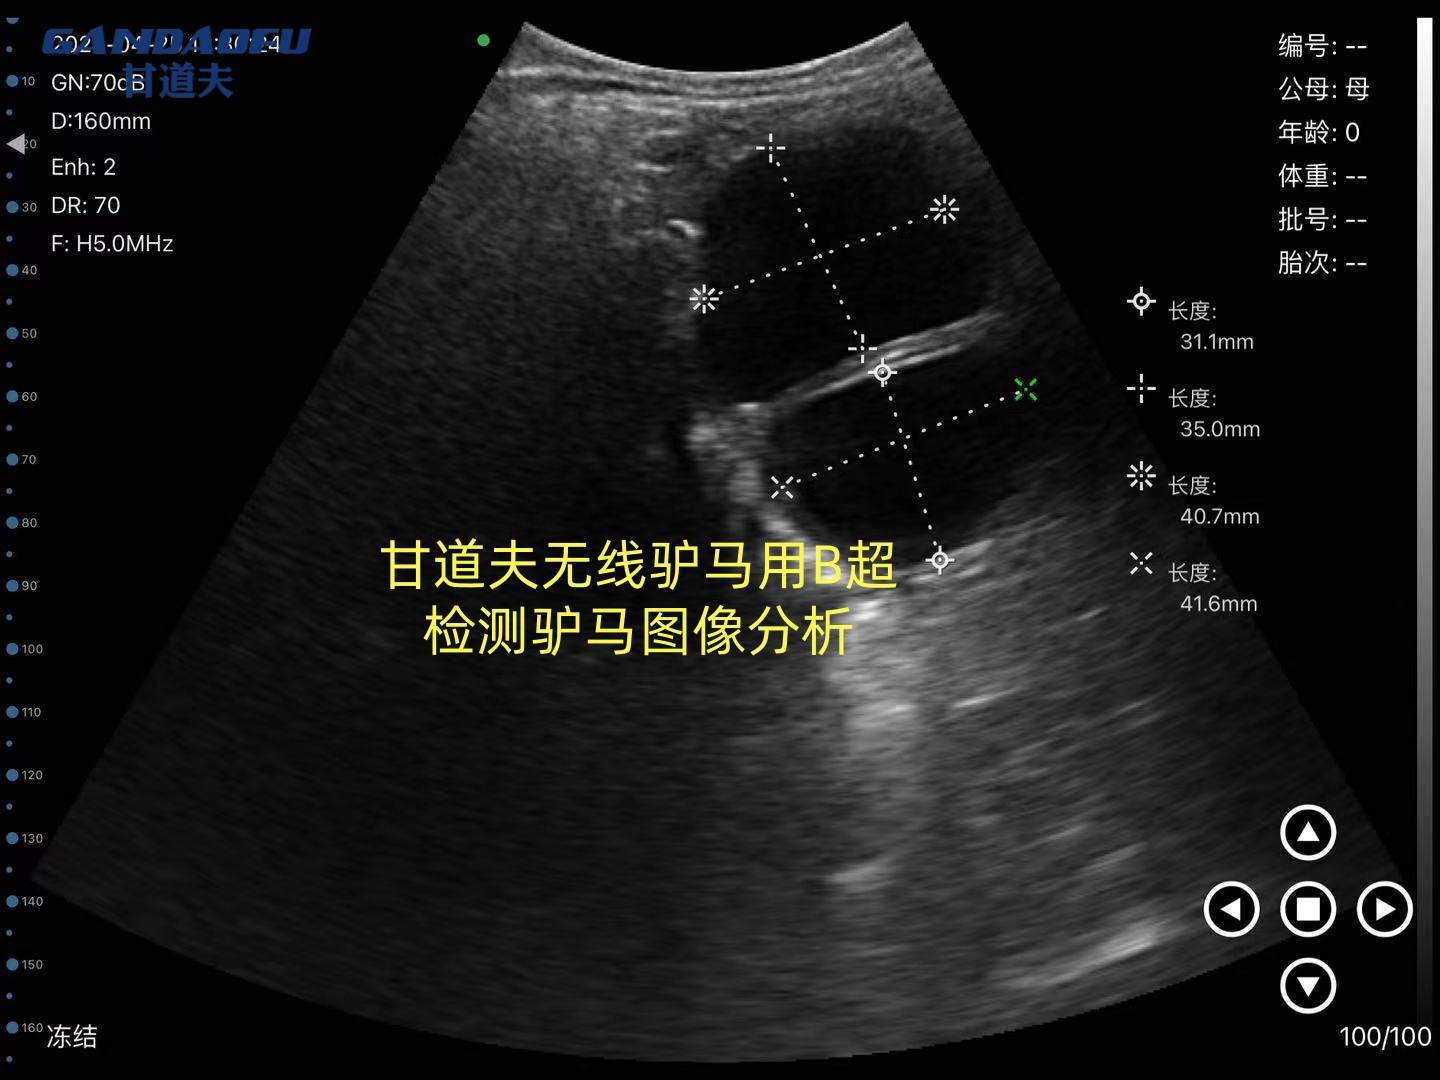

甘道夫 马用B超兽用B超检测驴马发情和牛一样都是在直肠内检测如图所示 直肠触诊:子宫张力增大,宫颈松弛(需专业兽医操作)阴道镜检查:黏膜充血潮红,黏液呈"冰柱状"结晶卵泡监测:通过B超追踪卵泡发育(成熟卵泡直径约4-5cm)。母马发情行为表现为 发情初期:吧嗒嘴、阴门轻度肿胀,见公马抬头竖耳但拒绝爬跨。发情高潮期:主动接近公马、频频排尿、阴门红肿、流黏液、拱腰叉腿接受交配。局限性:依赖经验,易误判,难以精确到排卵时间。马用B超技术培训实践操作驴马用B超验胎图像怎么看快来咨询甘道夫马用B超驴用B超厂家

马用B超直肠检测母马怀孕在母马配种后早14天可见孕囊("向日葵征")胎心监测:25天左右可检测到心跳(120-160次/分)注意:驴怀骡时可能出现假阴性孕酮检测:维持在>4ng/ml水平 中期诊断(30-180天)30天:子宫角不对称,孕角增大 60天:孕角如排球大小 90天:可触及胎儿浮动感,外阴观察妊娠3个月后:阴唇闭合呈"菊花纹"皱褶阴道检查:宫颈粘液栓形成晚期诊断(180天至分娩),腹围测量法妊娠8个月:腹围增加15-20cm胎动观察:右侧腹部可见明显胎动(妊娠7个月后)实验室检查乳汁/血液雌激素:分娩前2周显著升高直肠检查:可触及胎儿头部(骨盆入口处) 马用B超技术培训实践操作驴马用B超验胎图像怎么看快来咨询甘道夫兽用B超驴用B超马用B超厂家